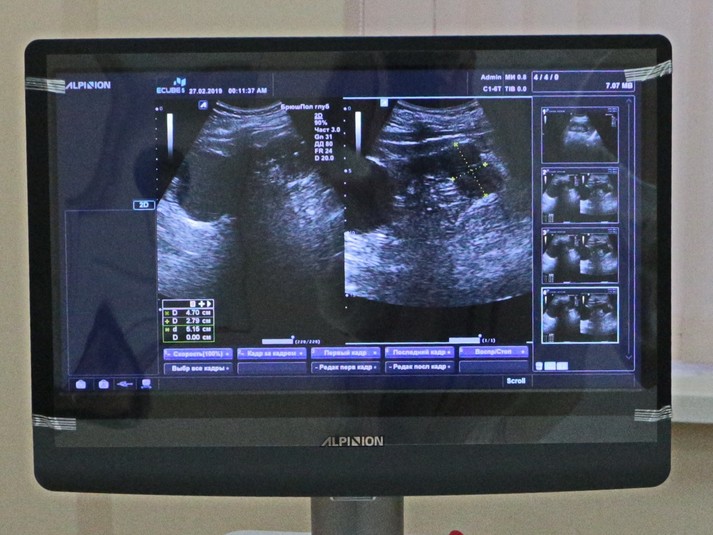

Для міської поліклініки №6 у рамках реалізації муніципальної програми «Здоров'я» за кошти міського бюджету закуплено сучасний апарат ультразвукової діагностики «Alpinion E CUBE 5» виробництва Південної Кореї.

Компактний ультразвуковий сканер забезпечує високу роздільну здатність і якість цифрового зображення, що несе відповідальність за достовірність і точність діагностики.

Апарат дозволяє проводити УЗД органів черевної порожнини, нирок, скелета і м'язів, щитовидної залози, а також використовується для проведення ультразвукового обстеження молочних залоз. Це актуально для міської поліклініки №6, на базі якої працює Міський центр здоров'я грудної залози.